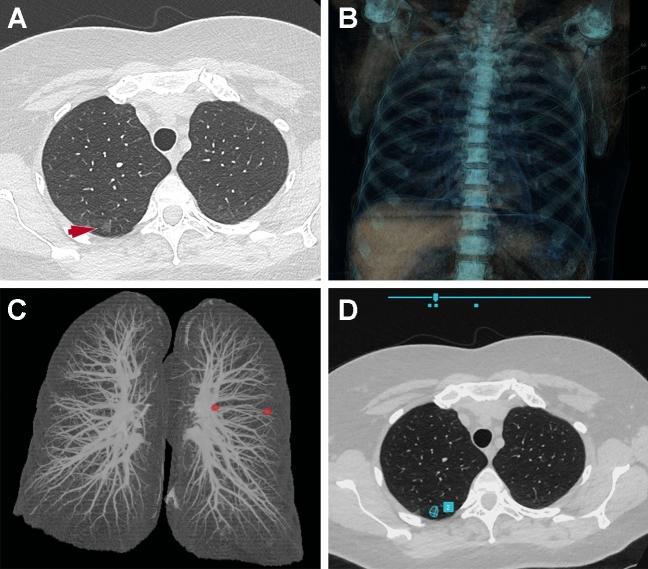

Artificial intelligence (AI) has been a very active research topic over the last years and thoracic imaging has particularly benefited from the development of AI and in particular deep learning. We have now entered a phase of adopting AI into clinical practice. The objective of this article was to review the current applications and perspectives of AI in thoracic oncology. For pulmonary nodule detection, computer-aided detection (CADe) tools have been commercially available since the early 2000s. The more recent rise of deep learning and the availability of large annotated lung nodule datasets have allowed the development of new CADe tools with fewer false-positive results per examination. Classical machine learning and deep-learning methods were also used for pulmonary nodule segmentation allowing nodule volumetry and pulmonary nodule characterization. For pulmonary nodule characterization, radiomics and deep-learning approaches were used. Data from the National Lung Cancer Screening Trial (NLST) allowed the development of several computer-aided diagnostic (CADx) tools for diagnosing lung cancer on chest computed tomography. Finally, AI has been used as a means to perform virtual biopsies and to predict response to treatment or survival. Thus, many detection, characterization and stratification tools have been proposed, some of which are commercially available.

人工智能(AI)是近年来非常活跃的研究课题,特别是在胸部影像学领域,AI 技术,尤其是深度学习技术,得到了广泛的应用。现在,我们已经进入了将 AI 应用于临床实践的阶段。本文的目的是回顾 AI 在胸部肿瘤学中的当前应用和前景。在肺结节检测方面,自 21 世纪初以来,计算机辅助检测(CADe)工具已经商业化。深度学习的兴起以及大型注释肺结节数据集的可用性,使得开发出了新的 CADe 工具,每个检查的假阳性结果更少。经典的机器学习和深度学习方法也被用于肺结节分割,从而实现了结节体积和肺结节特征的定量分析。在肺结节特征分析方面,使用了放射组学和深度学习方法。国家肺癌筛查试验(NLST)的数据允许开发几种计算机辅助诊断(CADx)工具,用于在胸部 CT 上诊断肺癌。最后,人工智能还被用作进行虚拟活检以及预测治疗反应或生存的手段。因此,已经提出了许多检测、特征分析和分层工具,其中一些已经商业化。